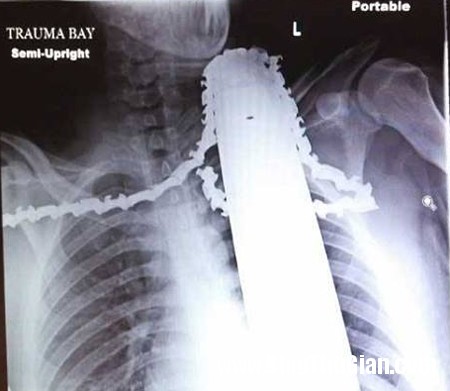

Hình chụp X-quang lưỡi cưa găm chặt vào cổ James.

James được đưa vào Bệnh viện Allegheny thuộc thành phố Pittsburgh để cấp cứu. Tại đây, bác sĩ Christine Toevs cho biết, lưỡi cưa đã may mắn không cứa vào động mạch mà chỉ chạm vào cơ của anh. Nếu ngay từ đầu đã rút lưỡi cưa ra, James sẽ bị mất máu rất nhiều và có thể gặp nguy hiểm tới tính mạng.